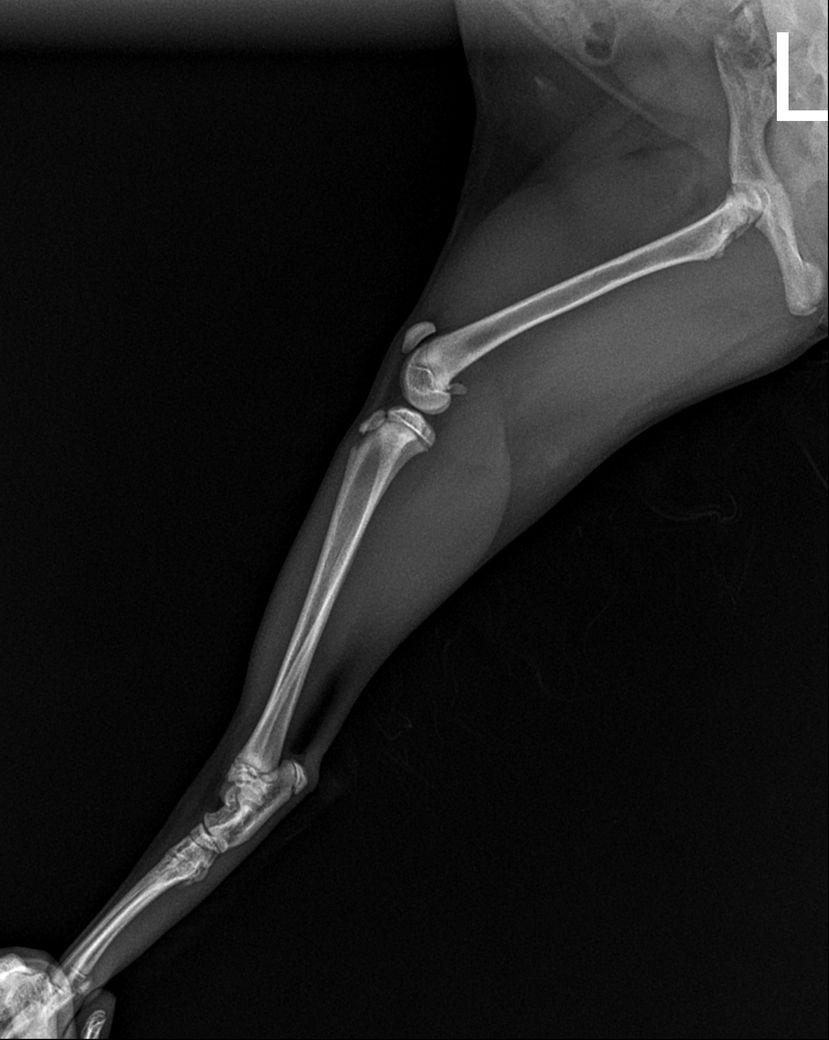

고양이 고관절 골절 진단받았는데 병원에서는 수복수술 해야한다고 하는데 자연적으로 붙는곳이아닌가요 ? 그리고 예후가 괜찮을까요 ? 수술한다고해서? 예후가 안괜찮다하면 어떤식으로 안좋을까요 ?

예, 사진상 우측 고관절의 관절면이 포함된 골절이기에 하중이 가해지는 장소인 바 자연 치유는 후천적 기형을 유도하게 되고, 수술을 하더라도 관절면이 포함된 상태로 예후는 불량한 수준입니다. 때문에 단순한 유합수술이 아닌 대퇴골두골목절단술을 동반해야 합니다.